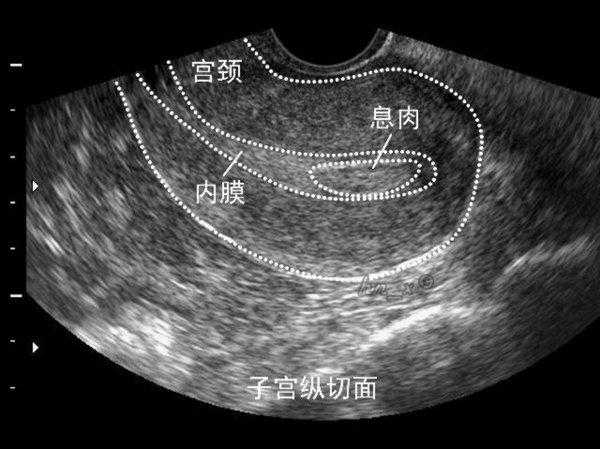

1、子宫内膜息肉是一种常见的妇科疾病,是子宫局部内膜过度生长的结果,可谓是宫腔里的不速之客。无症状女性常在体检(或因其他疾病如不孕,月经不规律做检查)时意外发现子宫内膜息肉。年龄增长与激素补充治疗是其高发主要原因。子宫内膜息肉有复发的倾向(2.5%-3.7%)。子宫内膜息肉不仅仅只有手术治疗,如果息肉较小,直径<1层面,且无症状,可以观察随诊。一年内自然消失吕伟率为27%。你刚做过手术,我不建议短期内再次手术,可以观察一段时间。

对你来说,子宫内膜息肉也可以影响月经,导致月经间期出血,月经过多,或不规则出血,甚至不孕。你已做息肉手术,建议先观察一段时间。另外,还应排除精神因素造成的月经不调。你正在做生育准备,往往会过度关注月经,精神压力过大,也可引起月经的一些变化。

子宫是孕育胎儿的暖房。在这一亩二分地上,任何不速之客都是不受欢迎的。对于患有息肉的不孕妇女,手术切除息肉有助于增加受孕的几率。据研究报道,进行试管婴儿的不孕妇女,子宫内膜息肉患病率为32%。也就是说,子宫内膜息肉与不孕有着密切联系。你已经做过两次手术,再次手术需要慎重。观察一段时间也是必要的,因为小的息肉可以自然消失。